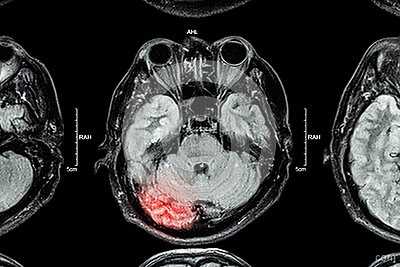

Осложнения сотрясения - мелкие кровоизлияния внутрь подпаутинного пространства. Гиперинтенсивные очаги мозга на МРТ ограничены. Усиленные пятна после сотрясения сочетаются с участками нормального или сниженного сигнала. Динамическое наблюдение позволяет визуализировать нормализацию состояния. Патология сохраняется при разрыве сосуда, расслоении сосудистой стенки (аневризме).

Сильный ушиб головного мозга может привести к переломам, обширным кровоизлияниям. Интенсивные очаги головного мозга на МРТ возникают вследствие скопления крови внутри подпаутинного пространства. Неоднородная плотность магнитно-резонансных томограмм характеризуется возникновением на снимках участков темного, белого цвета. Гиперинтенсивные пятна не имеют четких границ. Изображения свидетельствуют об отеках, скоплении кровяных сгустков.

Острая субдуральная гематома (оСДГ) малых размеров, но при этом визуализируется непропорциональный повреждению масс-эффект. Степень смещения срединных структур (подфальксное вклинение) больше, чем характерно для острой субдуральной гематомы. Отек ипсилатерального полушария головного мозга. Развитие отека мозга может быть внезапным и стремительным.